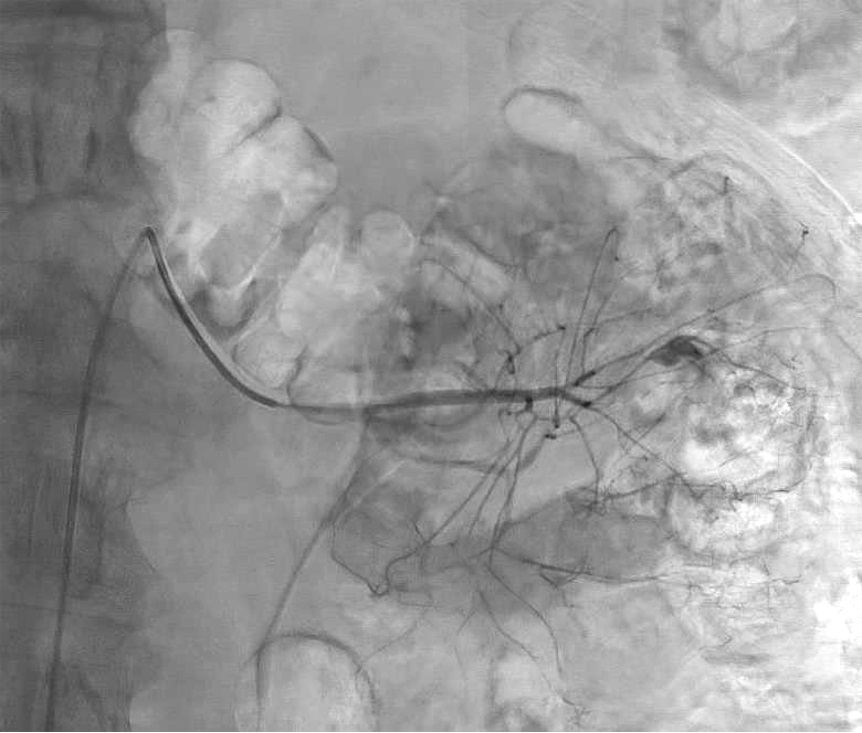

增强CT扫描

仍然不能确定具体出血血管 |